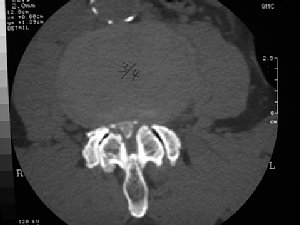

難病の頚椎後縦靱帯骨化症の手術前 |

手術後 | ||